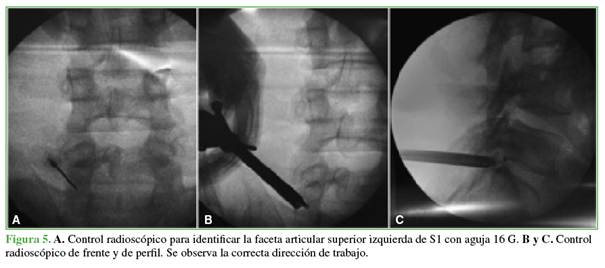

Discectomía endoscópica transfacetaria L5-S1

Bajo anestesia general, se coloca al paciente en decúbito prono. Mediante radioscopia directa en posición de frente, se marca con una aguja de 16 G en la punta de la faceta articular superior de S1. Se realiza una incisión cutánea de 8 mm y la apertura de la fascia lumbar. A continuación, se desciende la cánula de trabajo junto con el endoscopio. Se procede al fresado lateral de la faceta de la vértebra inferior con fresa diamantada. A medida que se genera el espacio en dirección medial y ventral, se desciende la cánula. Una vez localizada la cortical anterior de la faceta, se la reseca con una pinza Kerrison Rongeur de 3 mm. Luego, se efectúa un control radioscópico para confirmar la correcta dirección de trabajo (Figuras 5-7).